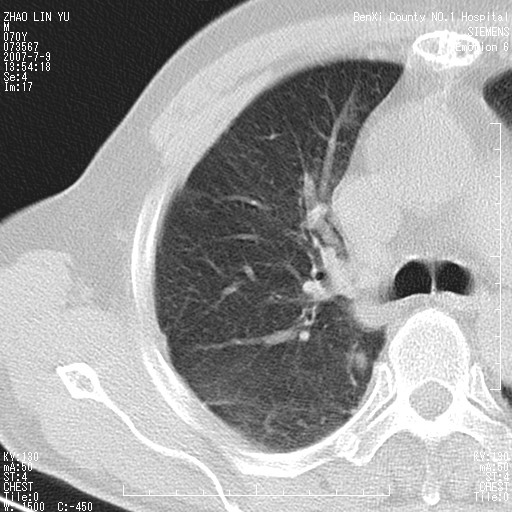

以下是引用王靖旗在2007-7-10 17:12:00的发言:[br] 男、70、咳嗽两个月,半年前换瓣手术,胸片未见异常,于昨天行x片发现右肺上野大片影,行ct扫描,这里是减薄图像,余肺正常。明天晚上会有增强扫描片,到时我会上传。[br][br] 冠状位请大家细看,应该是有意义的,[br][br] 请大家先看平扫发表意见。[br][br]

以下是引用zhangzhongshou在2007-7-10 21:43:00的发言:[br]右肺上叶周围型肺癌,以孤立型细支气管肺泡癌可能性大。